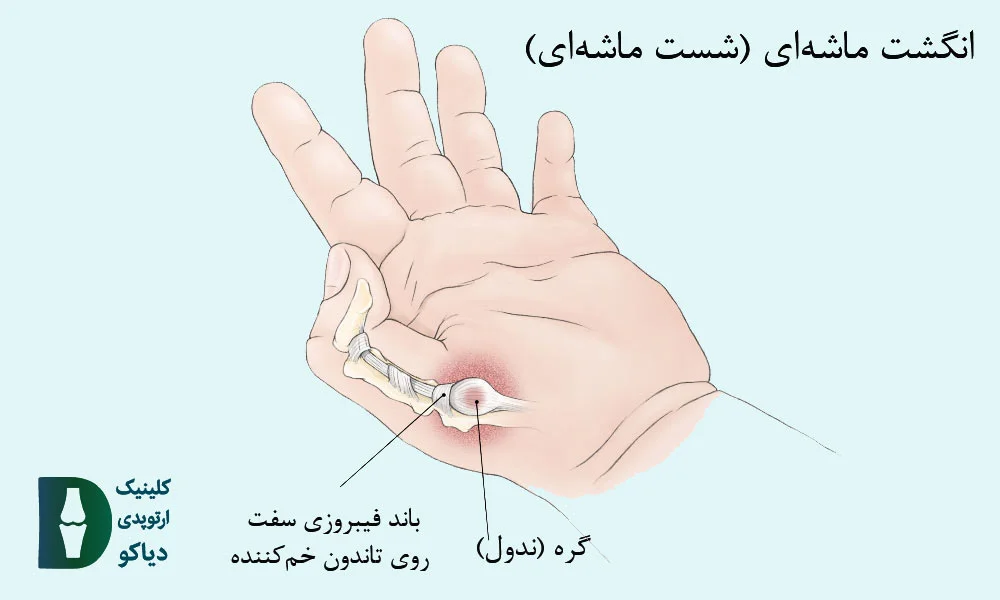

انگشت ماشهای در کودکان (بهویژه در شست) معمولاً بهصورت مادرزادی بروز میکند و برخلاف فرم اکتسابی در بزرگسالان، دردناک نیست، اما میتواند باعث گیرکردن دائمی انگشت در حالت خمیده شود. در این حالت، کودک قادر به صافکردن شست خود نیست، حتی با کمک دست دیگر و علت اصلی این مشکل، تشکیل یک گره کوچک (ندول) در تاندون خمکننده و تنگی غلاف اطراف آن است که مانع از حرکت روان تاندون میشود.

نتایج مطالعات روی بیش از ۴۰۰ کودک نشان داده است که درمان جراحی پس از دو سالگی، اثربخشتر و ایمنتر است و در هیچ موردی منجر به عود یا عارضه نشده، در حالیکه درمانهای غیرجراحی، بهویژه در کودکان بالای ۲ سال، در بیش از ۷۰٪ موارد موفق نبودهاند.

درمان غیرجراحی انگشت ماشهای در کودکان زیر ۲ سال تنها در ۳۰٪ و در کودکان بالای ۲ سال فقط در ۲۰٪ موارد موفق بوده، در حالی که جراحی در هر دو گروه سنی نزدیک به ۱۰۰٪ موفقیت بدون عوارض یا عود داشته است (منبع).